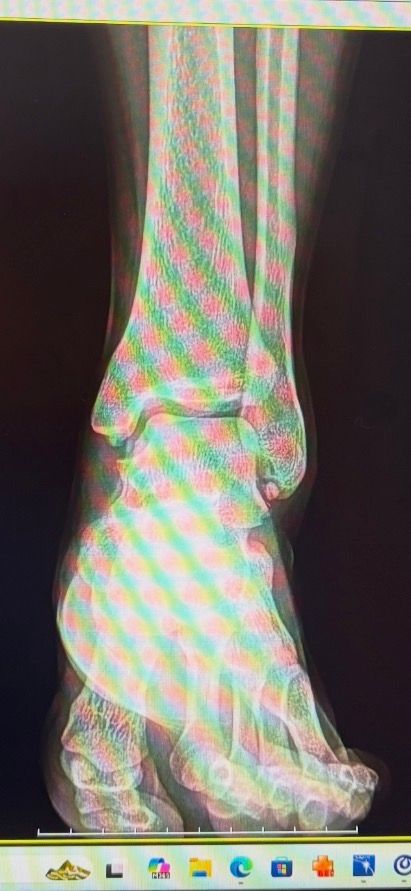

• 1번 째 사진

• 엑스레이 사진 확인했습니다. 발목 관절 전반적인 구조는 보이는데, 인대는 엑스레이에서 직접 보이지 않아 CT나 MRI 소견이 더 중요합니다.